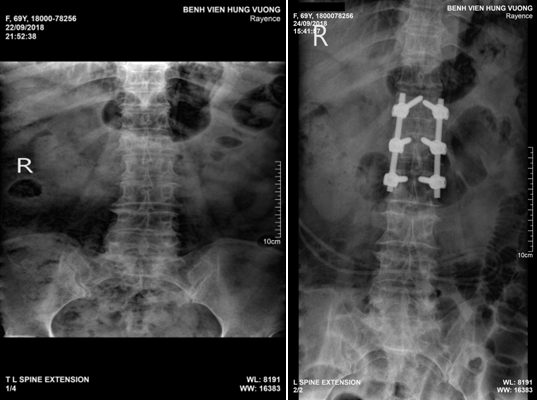

Bệnh viện Đa khoa Hùng Vương (Phú Thọ) vừa tiếp nhận chị B.T.H. (65 tuổi, ở Đoan Hùng, Phú Thọ) nhập viện trong tình trạng đau nhiều cột sống lưng và hạ vị.

Người đàn ông 51 tuổi (ở Tuyên Quang) phải phẫu thuật cố định đốt sống do ngã xuống từ độ cao 3m dẫn đến vỡ đốt sống thắt lưng, mất vững, thoái hóa đa tầng các đĩa đệm và đốt sống thắt lưng.